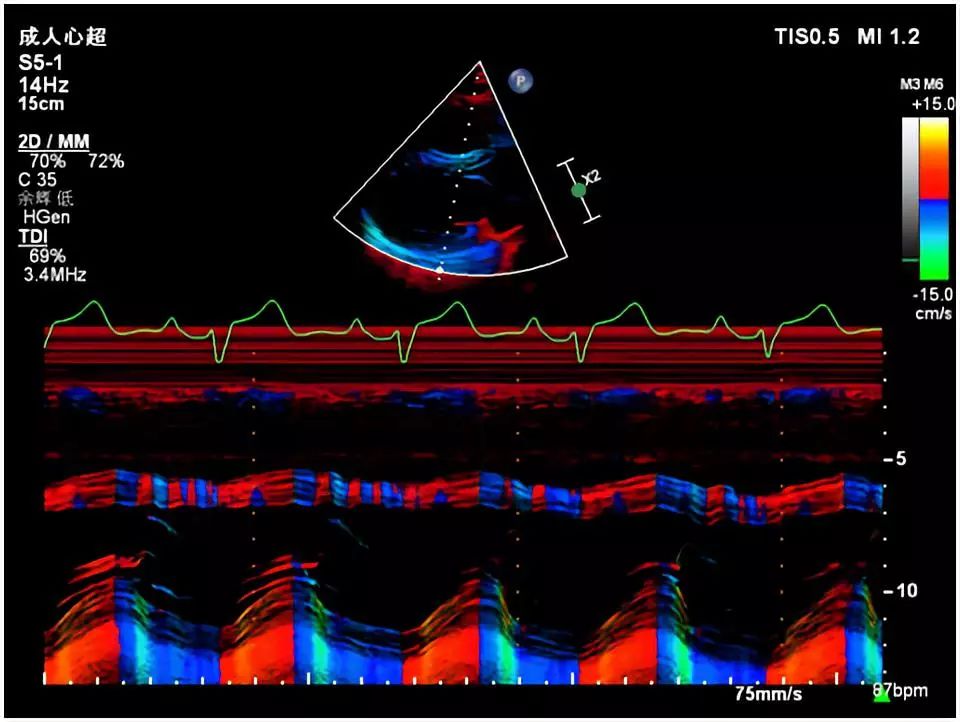

图3. 彩色M型超声显示右心室扩大,室间隔运动幅度减低并呈混合向运动,左心室后壁运动幅度显著增大